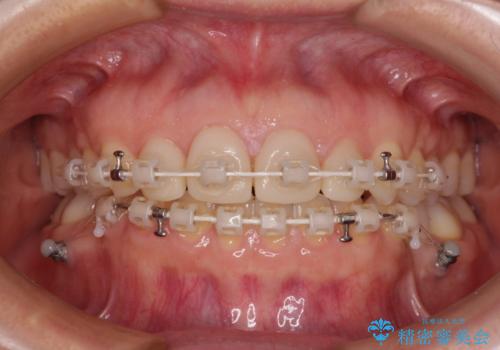

- 矯正装置

- 審美装置

下顎前歯は空隙歯列弓であったので、アンカースクリューとワイヤー装置を用いてスペースを閉じていくこととし、上顎前歯は矯正治療用の仮歯に置き換えた上で、仮歯の大きさを削って小さくしながら、上下前歯部の部分矯正を行うこととしました。

日本と海外を拠点に仕事をされていらっしゃるため、数ヶ月治療があいてしまうことがあり、期間はかかりましたが、2年間で望み通りの前歯に仕上げることができました。